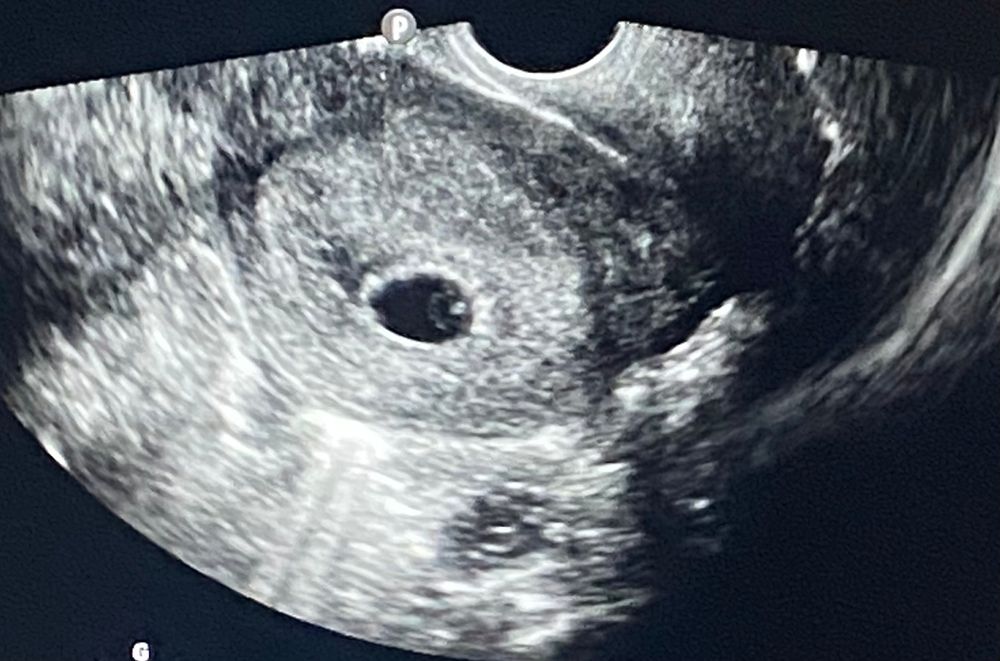

Гематома 24дпп

Результаты УЗИ

Здравствуйте девочки, сегодня 24дпп первое узи, нашли эмбрион 🙏🏻 есть гематома, кто разбирается , большая ? Страшно очень(